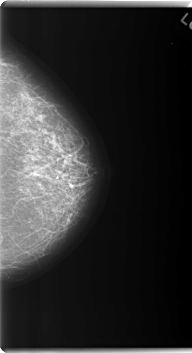

C_0179_1.LEFT_CC

LEFT_CC LINES 6000 PIXELS_PER_LINE 3256 BITS_PER_PIXEL 12 RESOLUTION 50 NON_OVERLAY